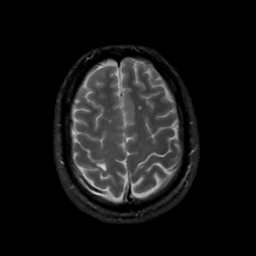

MR Study #15, June 9, 1991 -- Slice #40